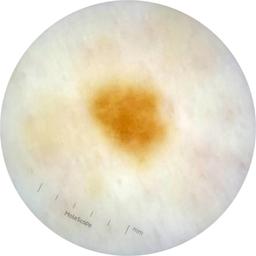

MEL-SELF - Dermoscopic

- Name: MEL-SELF - Dermoscopic

Dermoscopic lesion images (close-up views of benign and malignant lesions) from the MEL-SELF trial (the Melanoma Self Surveillance trial).